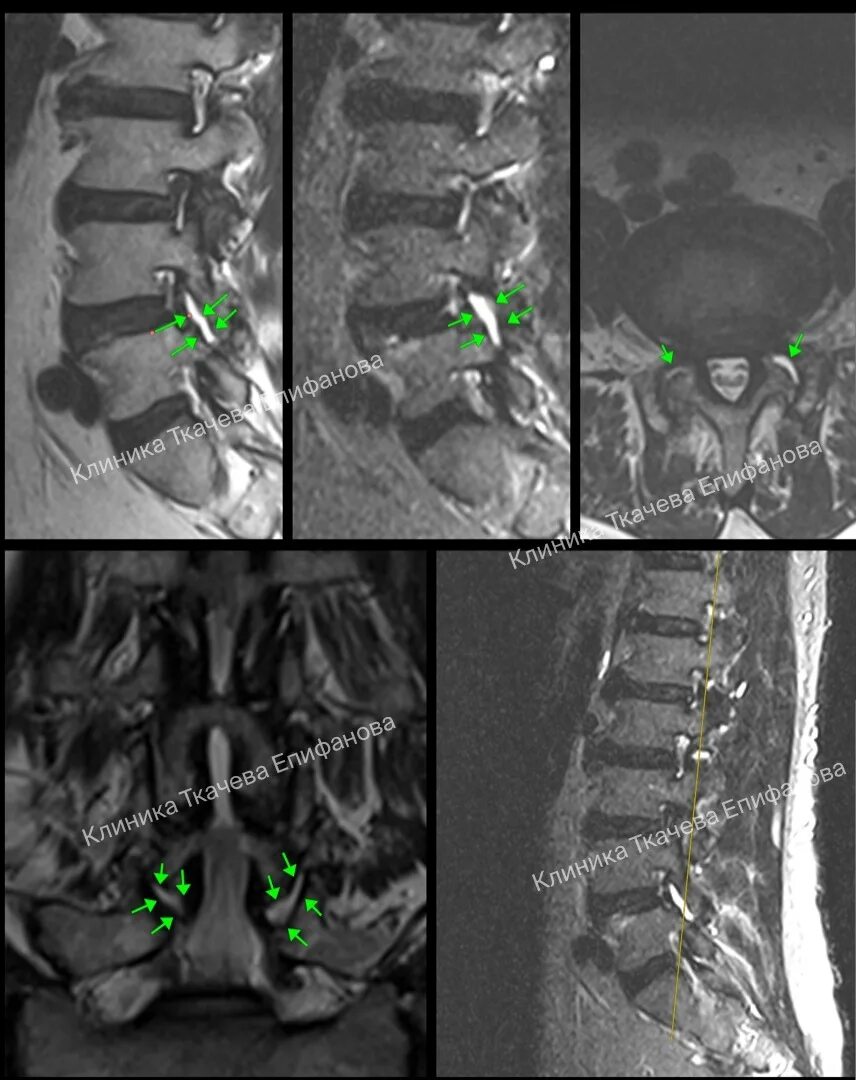

Артроз фасеточных суставов позвоночника